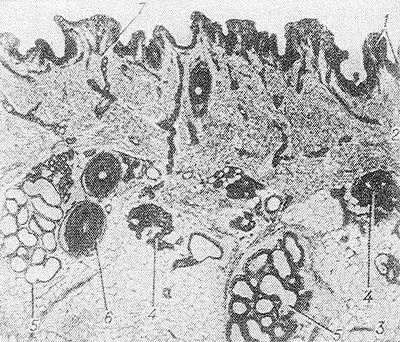

Рис. 2. Микропрепарат кожи подмышечной области: 1 — эпидермис, 2 — дерма, 3 — подкожная клетчатка, 4 — концевая часть эккринной потовой железы, 5 — концевая часть апокринной потовой железы, 6 — волос, 7 — потовый проток; окраска гематоксилин-эозином; х 100.

Они представляют собой простые трубчатые железы со свернутыми в клубки концевыми частями. Каждая Потовая железа состоит из концевой части (pars terminalis), или тела, и потового протока (ductus sudoriferus), открывающегося наружу потовой порой (porus sudoriferus). Наличие пор на коже впервые обнаружил в 1687 г. М. Мальпиги. Считается, что Потовые железы были открыты в 1833 г. Я. Пуркинье, однако еще в 1662 г. Стенон (N. Ste-non) описал маленькие подкожные железы, связанные с кожей тончайшими каналами. По характеру секреции (см.) Потовые железы делят на эккринные (мерокринные) и апокринные (см. Железы), различающиеся по развитию, морфологическим признакам и функциональному значению (рис. 1 и 2).